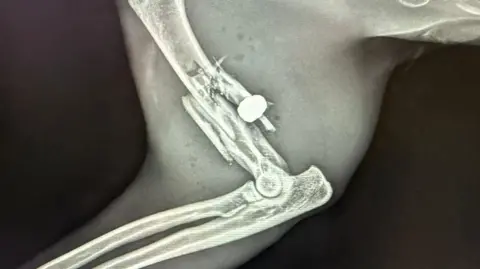

The initial assumption was that Simba had been in a road traffic accident but X-rays confirmed he had been shot with a pellet gun.